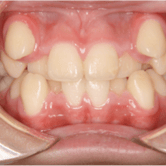

Maloclusión

La maloclusión es una alineación incorrecta de los dientes y la mordida, que puede ser hereditaria o causada por hábitos como el uso prolongado del chupete o la succión del pulgar.

Los padres pueden notar que los dientes de sus hijos están torcidos, apiñados o que la mordida no cierra correctamente. La maloclusión puede afectar la masticación, el habla y la apariencia.

El tratamiento puede incluir ortodoncia para corregir la alineación de los dientes y mejorar la función oral.